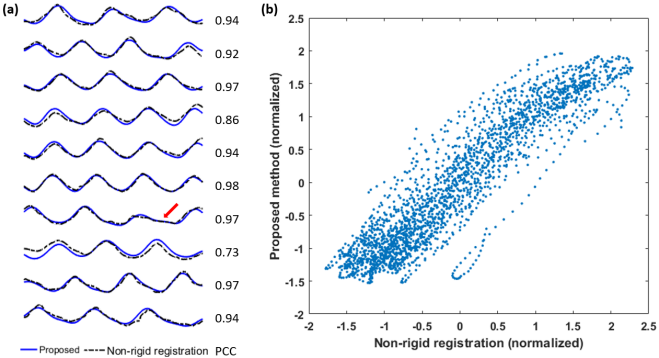

Table 1 summarizes the Pearson correlation coefficients for all the volunteers. The results show that the extracted respiratory signal has a high, positive correlation with the reference in all cases. This method is also robust across different respiratory patterns. Fig. 3 shows representative results from two volunteers, one with short respiratory cycles and the other with long cycles. As highlighted by the red arrow, this method is also tolerant of irregular motion. For some slices in Fig. 3, the difference between the reference and the proposed method is more pronounced. This is expected because the two methods measure different quantities: the proposed PCA-based method extracts the respiratory motion from the entire image, while the non-rigid image registration only tracks the motion in a small user-defined ROI.